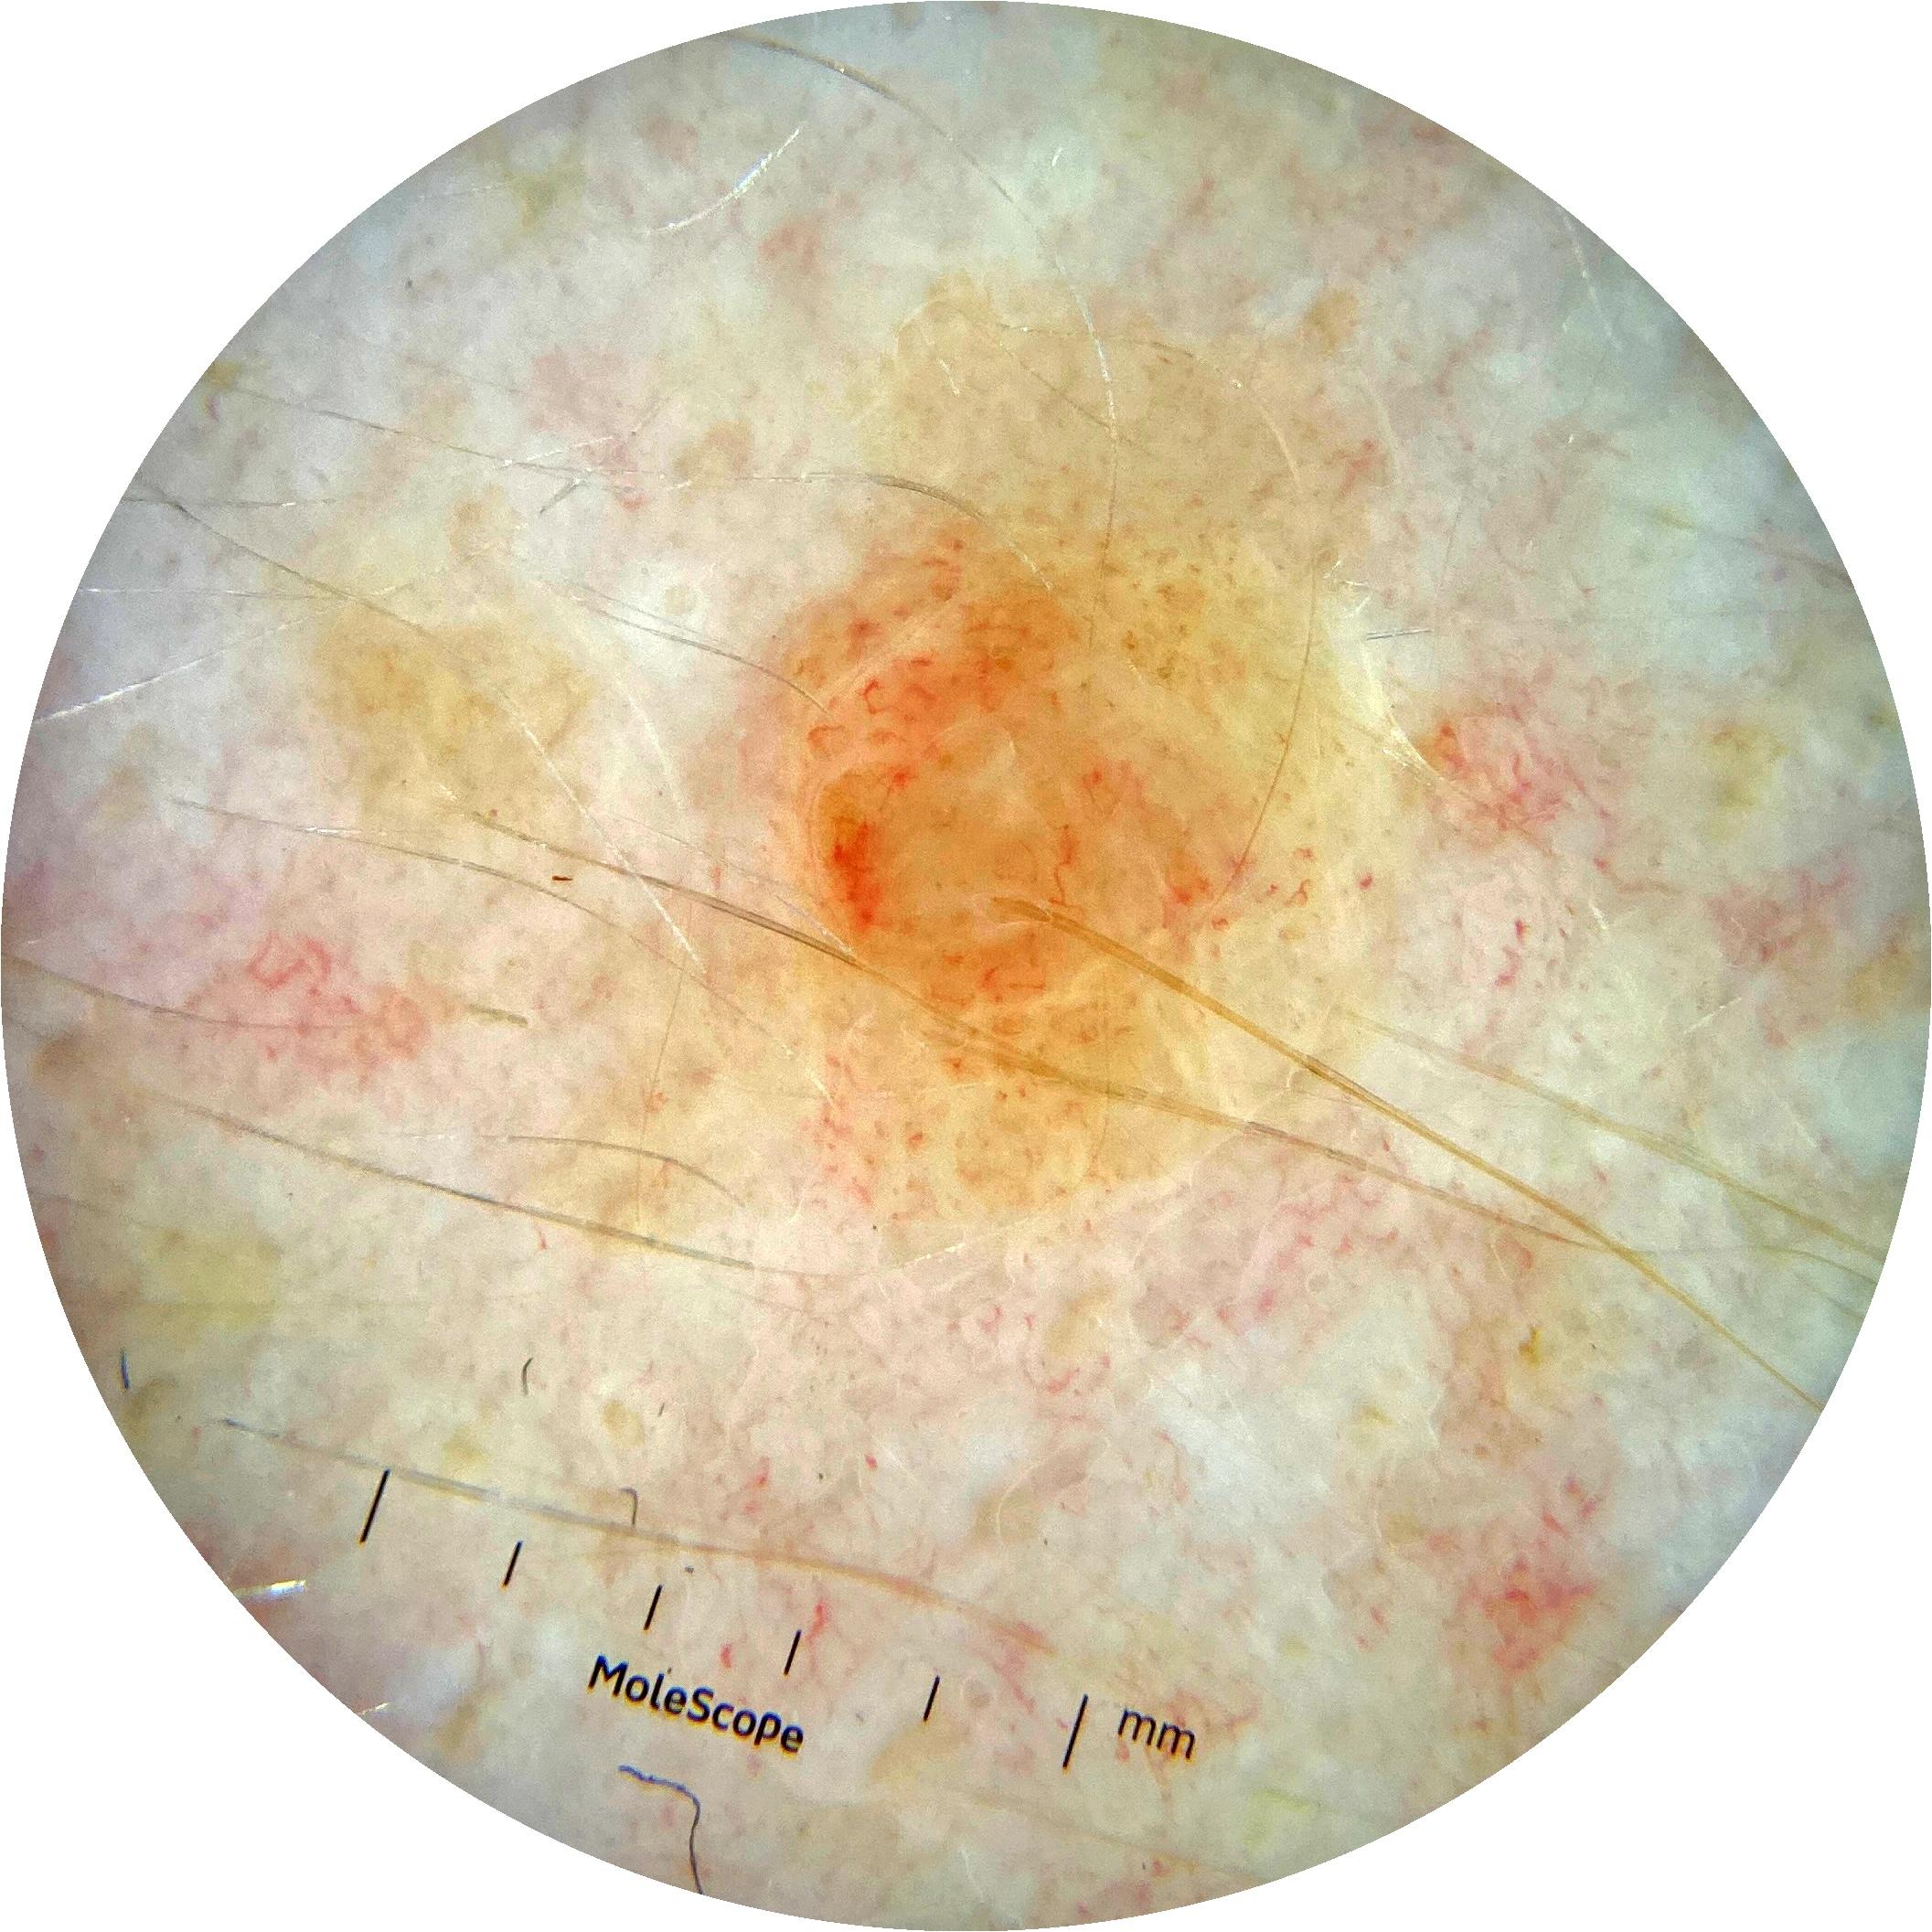

ISIC_3176953

2135 x 2135

diagnosis_1 Malignant

diagnosis_2 Malignant adnexal epithelial proliferations - Follicular

diagnosis_3 Basal cell carcinoma

image_type dermoscopic